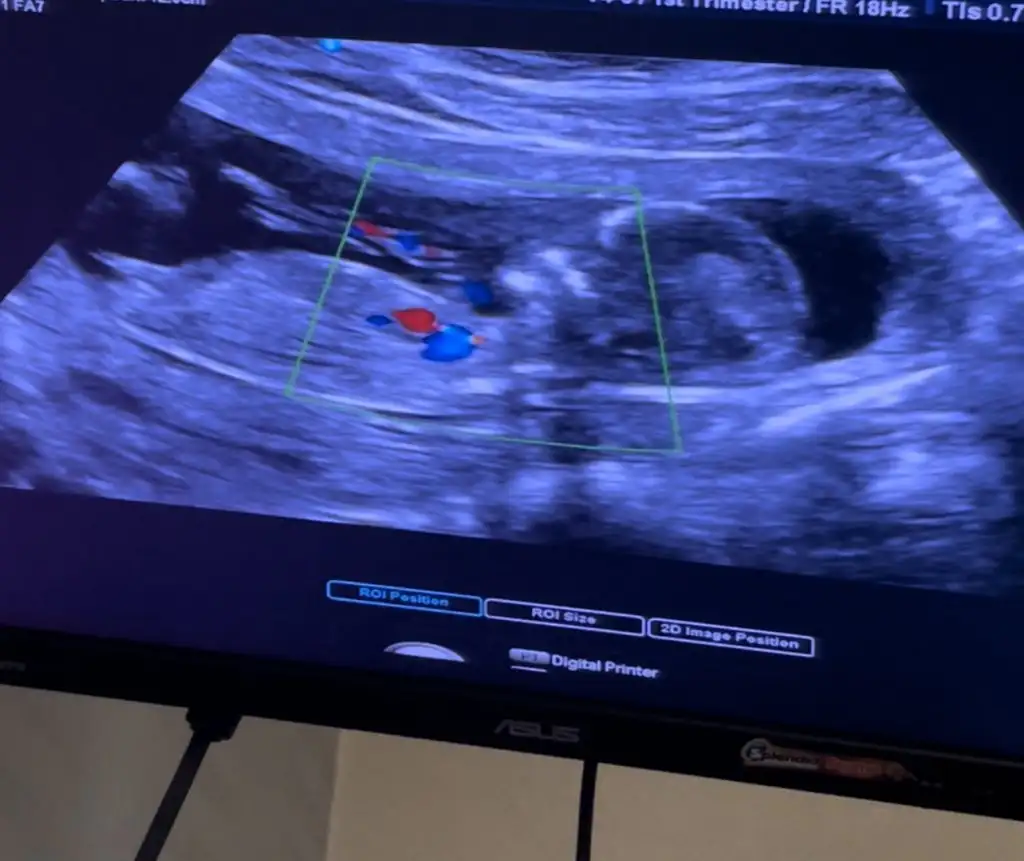

Merhaba nub teorisinden anlayan arkadaş varsa bakabilir mi 13 haftalık

• 04BFB7BF-205C-483A-A485-F2730229FC5F.webp

19,8 KB · Görüntüleme: 99